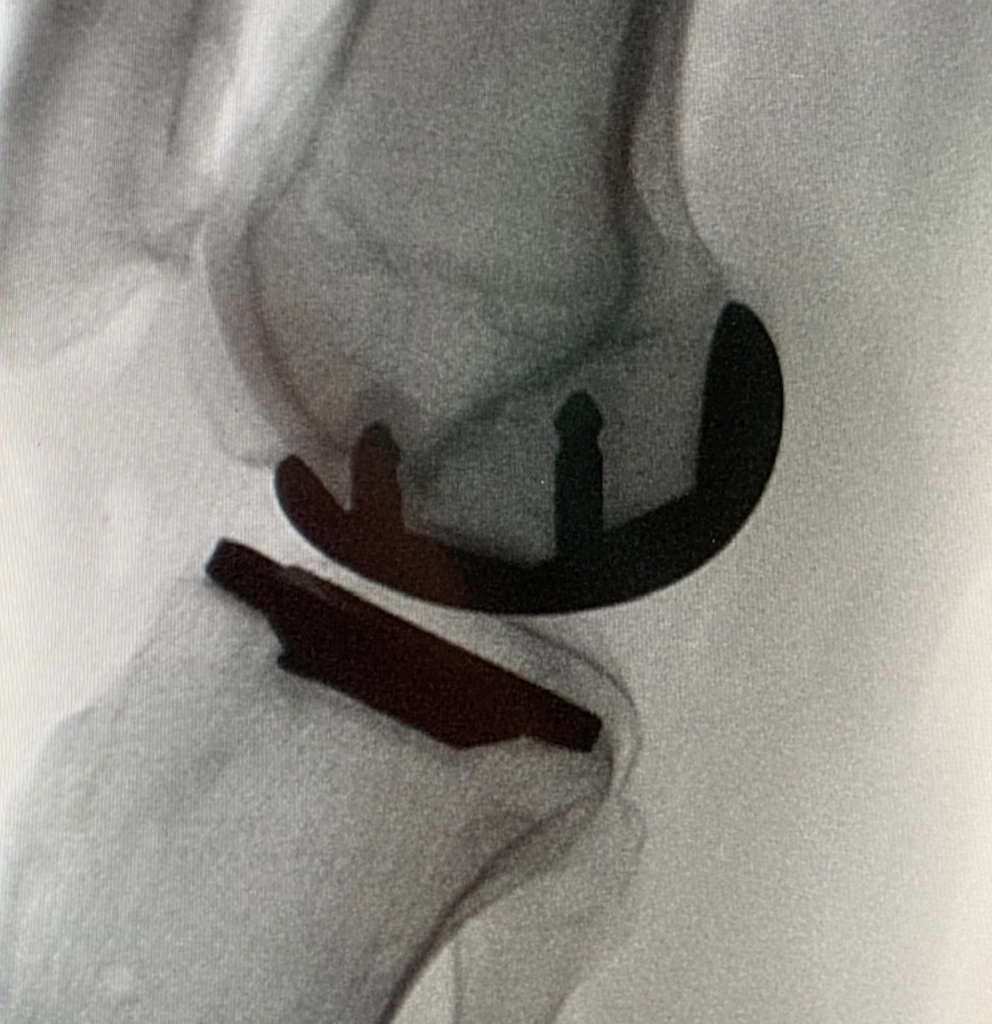

Möglich macht dies der von einem Chirurgen kontrollierte neuartige „VELYS™ Robotic-Assisted Solutions (VRAS)“-Roboter-Assistent, der in sämtliche Richtungen bewegt werden kann, um die beste Position beim Eingriff für ein künstliches Kniegelenk zu erreichen.

Beide observierten jeden Winkel der OP und die Positionierung des Gelenkersatzes in Echtzeit auf einer Monitorscreen. Vorteil des Roboter-Assistenten dabei: Er verriegelt die Bewegung der Ausrüstung, damit sie nicht von der vorgegebenen Position abweicht. So werden Komplikationen vermieden.